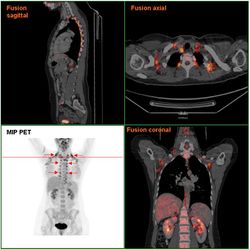

Этим открытием мы обязаны появлению нового метода визуализации активного метаболизма в ткани – позитронно-эмиссионной томографии, объединенной с компьютерной томографией (fused PET-CT), показавшей, что взрослый человек имеет около 20-30 граммов (так мало) функционального бурого жира, преимущественно в надключичной области.

PET-CT регистрирует метаболическую активность ткани, и на правом рисунке мы видим, как нарастает активность бурого жира в ответ на холодовой стресс у взрослого человека.